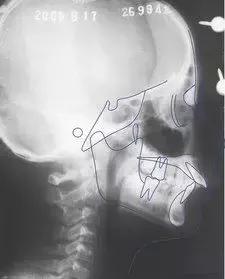

④X线片(全口曲面断层片、头颅侧位片等)。